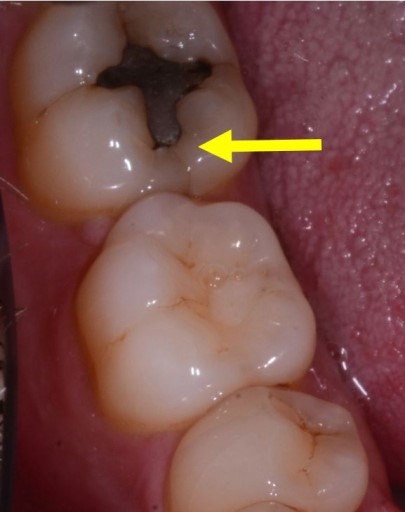

To bring this thought process into play on an actual case, let’s look at a case I had in my office. Preoperatively, the lower second molar had a relatively small failing alloy and looked to have a craze line over the mesial marginal ridge, as noted in the photo below.

There was also a more suspicious possible fracture, pictured below.